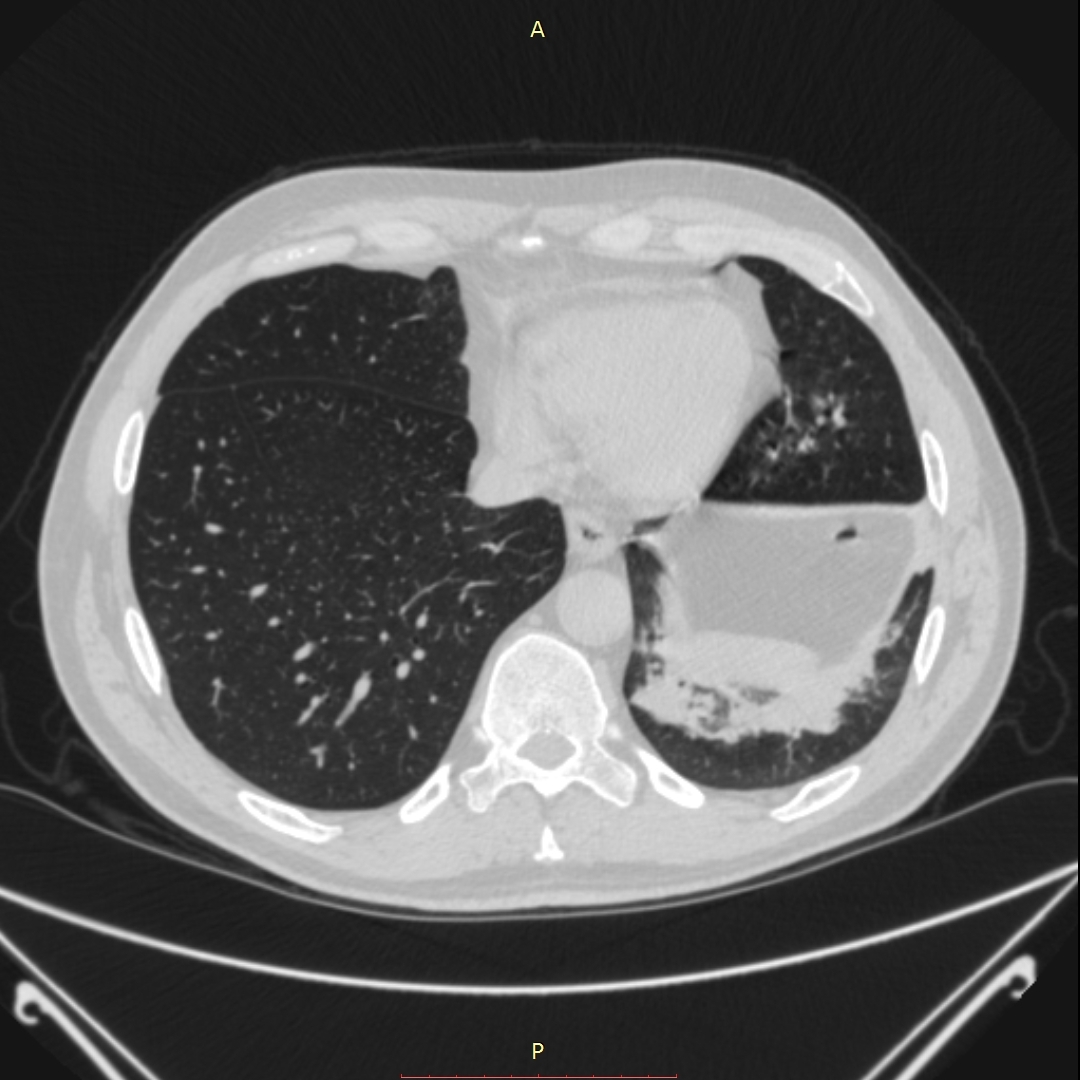

პაციენტი 52წლის მამაკაცი ერთი თვის ანამნეზით. გულმკერდის კტ კვლევით აღმოჩნდა 3,9-3,6სმ ზომის სუბკარინული ქსოვილოვანი კონგლომერატი, რომელიც იჭრება მარცხენა მთავარ ბრონქში და მთლიანად ახშობს მას, ნაწილობრივ ახშობს მარჯვენა ზ/წილოვან ბრონქს. ბიოფსიის მორფოლოგიით დადგინდა ბრტყელუჯრედოვანი გაურქოვანებელი ტიპის კარცინომა. პაციენტის მდგომარეობა დამძიმდა, მოხრჩობის შეტევების გამო ჰქონდა უძილობა. საციცოცხლო ჩვენებით პაციენტს ჩაუტარდა ლაზერული რეზექცია რიგიდული ბრონქოსკოპით, VELASTM 30W ქირურგიული დიოდის ლაზერული სისტემის გამოყენებით. მანიპულაციის დამთავრებისთანავე პაციენტის სუნთქვითი მონაცემები მყისიერად გაუმჯობესდა.

- გულმკერდის კტ რეზექციამდე 1 კვირით ადრე 2

მარცხენა მთავარი ბრონქის სანათური თითქმის მთლიანად დახშულია სიმსივნური წარმონაქმნით.

აღინიშნება მარცხენა ქვედა წილის ატელექტაზი.